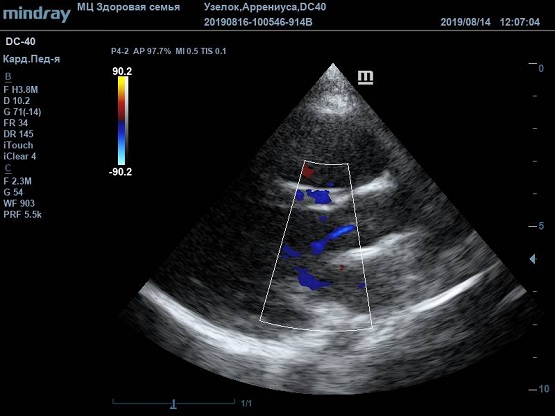

Существует вариантная анатомия, например, наросты Ламбла или гипертрофия узелков Аррениуса на полулуниях аортального клапана. Узелки и наросты увеличивают занимаемый объем полулуния, при этом нарушая конгруэнтность поверхности створок или полулуний клапана. В итоге закрытие осуществляется не полностью, и возникает легкая недостаточность. Именно такие случаи часто обнаруживаются у детей и не требуют специального лечения или пристального наблюдения.

Найти их очень просто, достаточно сечений LAXLV (длинная ось) и SAXBASE (короткая ось). Специфические крупные шаровидные структуры – узелки Аррениуса - на кончиках полулуний клапана обнаружил ультразвуковой прибор Mindray DC-40. В цветовом допплере без труда определяется аортальная регургитация легкой степени. Оценить её можно в CFM по соотношению JW/LVOT.

Приборы среднего класса прекрасно справляются с этой задачей. Чтобы использовать возможности прибора на максимум необходимо уменьшить поле обзора (Front of view - FOV), тогда увеличится частота кадров и качество картинки при поиске мелких структур. Также частота кадров увеличивается при снижении уровня persistence, что актуально для детского возраста и высокой частоты сокращения сердца.